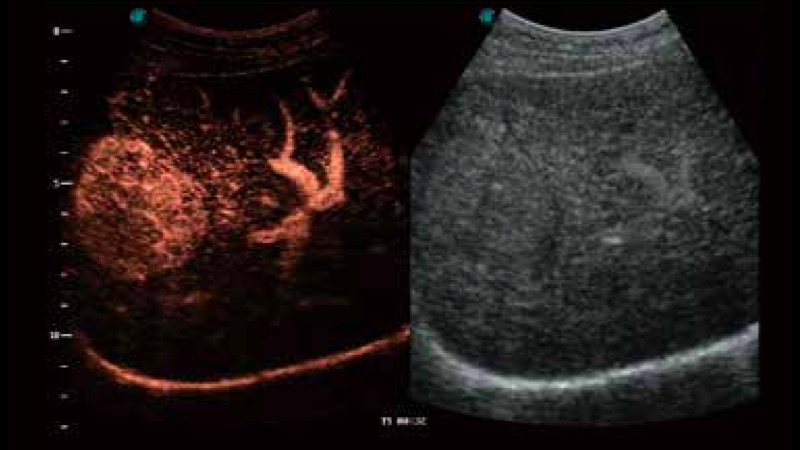

SR Flow高分辨率血流成像

高分辨率血流成像技术提高了对低速血流信号的检测能力。在提高空间分辨率的同时,也克服了血流外溢现象,为用户提供更加真实的血流动力学信息。

造影成像

造影成像功能和定量分析工具包使医生能够更好的评估血流灌注情况。独特的动态声压控技术有效控制造影剂的声压,保证更长的造影剂持续时间,更好的观察病变灌注的延迟相位。

临床图像